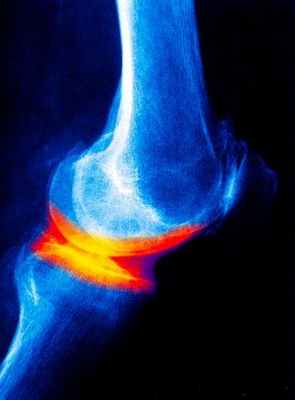

При появлении симптомов деформирующего остеоартроза необходимо записаться на консультацию к травматологу-ортопеду. Среди исследований при ДОА информативен рентген, КТ и МРТ. На рентгене в пользу остеоартроза свидетельствует сужение межсуставное щели, наличие кист и разрастаний остеофитов. Пункция и биопсия хрящевой ткани проводится для исключения других заболеваний соединительной ткани.

- рентгенодиагностику, благодаря которой будет четко заметна степень сужения щели сустава, размеры и локализацию разрастаний, особенности изменения кости;

Рентгенологические методы исследования дают, как правило, достаточную информацию о наличии дегенеративных изменениях в суставе. В зависимости от рентгенологической картины проводится и классификация остеоартроза:

- 0 отсутствие рентгенологических признаков остеоартроза

- 1 стадия – кистозная перестройка костной структуры ткани появление маленьких остеофитов признаки линейного остеосклероза

- 2 стадия остеосклероз, более выраженный и появляются признаки сужения суставной щели.

- 3 стадия выраженный остеосклероз остеофиты становятся большими, суставная щель значительно сужается.

- 4 стадия остеофиты более массивные суставная щель практически не визуализируется деформация эпифизов костей их уплощение.

Рентгенологическое исследование суставов.